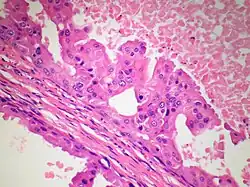

Fig. 2 Breast apocrine carcinoma

Fig. 3 Breast apocrine carcinoma

The microscopic histopathology of PACB tumors prepared with hematoxylin and eosin staining shows that >90% of the tumors consist of apocrine gland-like tissue. The lesions must also show that tumor cells have broken through their ducts of origin to invade adjacent tissue in at least one area. Most of the tumor cells (termed type A cells[15]) typically appear somewhat more irregular than normal apocrine gland cells. They have abundant eosinophilic (i.e. pink due to the uptake of the eosin dye) cytoplasm which contain numerous granules[11] and large mitochondria.[15] Their nuclei are large, variably sized and shaped, have multiple nucleoli (which are eosinophilic[11] and may be distinctively large in size[14]), and are surrounded by highly visible nuclear membranes. The cells are arranged into solid sheets, nests, papillae, and/or cords (see Figs. 1 and 2).[11] The tumor cells' cytoplasmic granules test positive when treated with the PAS diastase stain.[16] Binucleated cells, i.e. cells with two nuclei, are common.[10] Less commonly, type B apocrine cells are present; these cells have a more foamy and vacuolated cytoplasm (i.e. containing multiple vacuoles) than type A cells[15] and often resemble foamy histiocytes or sebaceous gland cells.[17] The tumor cells have low to moderate rates of proliferation based on their Ki-67 protein levels.[7] PACB tissues may have localized areas that contain mucin-like secretions within their luminal ducts,[10] localized areas of necrosis (i.e. foci containing dead or dying cells), and/or microcalcifications spotted throughout the apocrine tissue.[11] The stroma (i.e. connective tissue between the sheets, nests, papilla and cords of cells) typically contains non-malignant, infiltrating lymphocytes (see Fig. 3). In an examination of 41 PABC tumors, 33 (80.5%) had <50% of their stroma tissues infiltrated with these cells while 8 (19.5%) had ≥50% of their stroma tissues infiltrated with them. Tumors with ≥50% of their stroma infiltrated with lymphocytes tended to have carcinoma cells that had high rates of proliferation.[11] Metastatic and recurrent PACB tumors have a histopathology similar to their original primary tumors.[14]